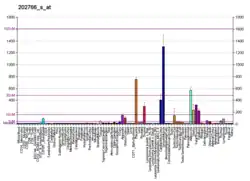

Fibrillin-1 is a protein that in humans is encoded by the FBN1 gene, located on chromosome 15.[5][6] It is a large, extracellular matrix glycoprotein that serves as a structural component of 10–12 nm calcium-binding microfibrils. These microfibrils provide force bearing structural support in elastic and nonelastic connective tissue throughout the body. Mutations altering the protein can result in a variety of phenotypic effects differing widely in their severity, including fetal death, developmental problems, Marfan syndrome or in some cases Weill-Marchesani syndrome.

Function

Fetal cardiovascular development

The FBN-1 gene is involved in a variety of embryonic developmental programs. The microfibrils that are made from fibrillin-1 contribute to both elastic and non-elastic structures. The formation of the elastic fibers in the heart valves and the aorta require the involvement of both FBN-1 and FBN-2.[10] It has been shown that both FBN-1 and FBN-2, along with the other components of elastic fibers, are expressed in the embryonic semilunar valves as early as 4 weeks of gestation.[11] These molecules interact to form the elastic fibers in the ventricularis layer of the semilunar valves. Fibrillin-1 and fibrillin-2 are also crucial for the development of elastic fibers in the aorta. While expression of fibrillin-2 decreases significantly after fetal development, the expression of fibrillin-1 continues into adulthood. This supports the idea that fibrilin-2 dictates the development of early elastic fibers, while fibrillin-1 provides the structural support of mature elastic fibers.[11]